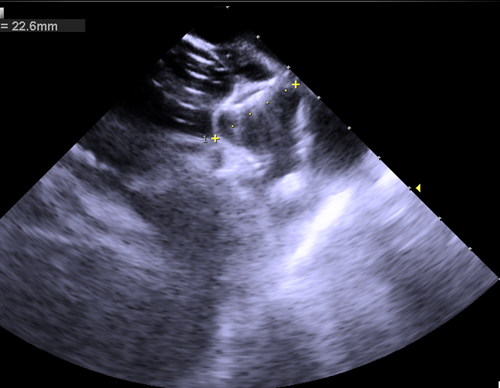

三维心腔内超声指导下成功植入封堵器

术后三维心腔内超声复查左心耳稳定性

经过术前准备,手术顺利开展,整个手术过程不到2小时,三维心腔内超声在术前对左心耳大小进行测量,术中指导房间隔穿刺,术后评估封堵位置及稳定性,术后李奶奶自述没有任何痛苦,在手术台上睡了一觉就解决了房颤对她带来的困惑,术后恢复已出院。